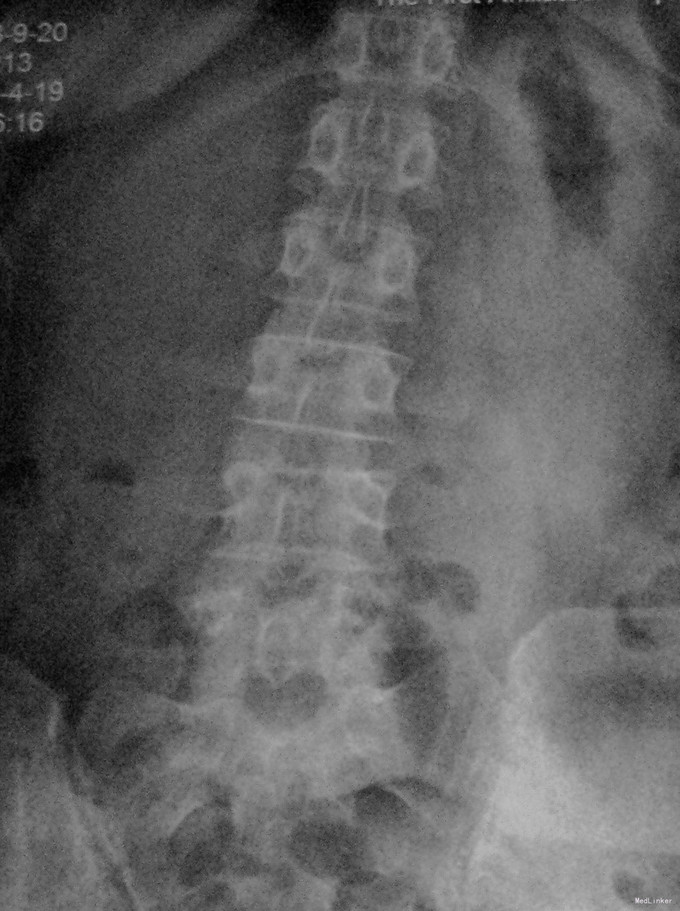

查体:脊柱生理弯曲存在,腰椎活动受限,L4/L5棘突压痛叩痛,叩击痛。双侧直腿抬高试验(-)。双下肢皮肤感觉正常,双侧髂腰肌、股四头肌、双侧胫前肌、踇背伸肌肌力Ⅳ级,腹壁反射、肛门反射正常,两侧膝正常,双侧踝反射未引出。双侧Babinski征(-),双侧皮温及色泽正常,双侧足背动脉搏动良好。 辅助检查:X光片示:动力位片显示腰椎4/5椎间失稳。MRI检查显示:腰4/5椎间盘突出,黄韧带肥厚致椎管狭窄,相应节段硬膜囊受压改变。

诊断:腰4/5椎管狭窄并失稳症。 治疗:给予行后路腰4/5右侧椎板间开窗减压椎间盘摘除并肥厚黄韧带切除+棘突间wallis固定术。